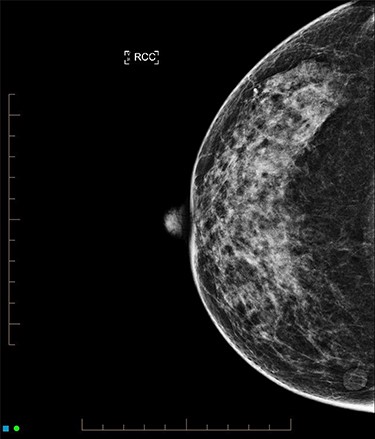

Core biopsy of the right breast demonstrated a high-grade ductal carcinoma in situ (DCIS) (Fig. 4), whilst staging computed tomography and bone scan showed no evidence of distal disease. Magnetic resonance imaging (MRI) identified a resectable 60-mm area in the right outer quadrant. AB underwent an oncoplastic right wide local excision with sentinel lymph node biopsy (SLNB), subsequently requiring an axillary dissection due to macrometastatic axillary disease. Histopathology showed multifocal high-grade invasive ductal carcinoma with immunotyping of Grade 3, PR ++, HER-2 negative, resulting in an adjuvant chemotherapy regime of cyclophosphamide and doxorubicin. The left breast was monitored without change during this time. Fully fractionated whole breast radiotherapy with boost to the tumor bed and regional lymph nodes is scheduled, alongside risk reducing endocrine therapy.